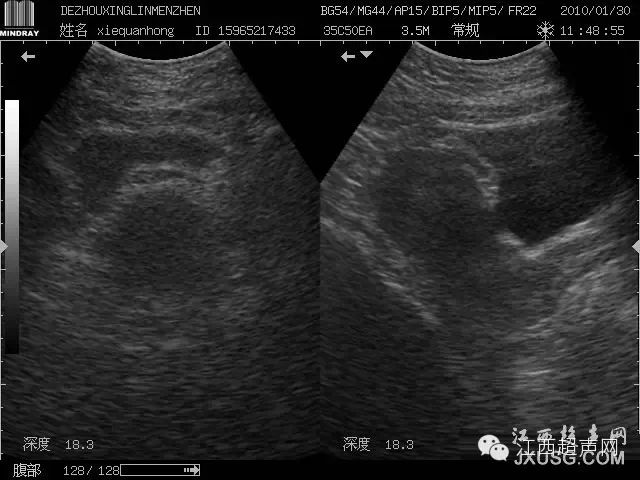

55.患者女,因左侧腰背部疼痛到我院门诊就诊,当时泌尿科考虑为泌尿系结石就申请B超检查:

而且前一段时间CT室的人和我们说,我们超声诊断的肝内多发性囊肿在CT增强时部分囊性占位内可见增强剂充盈,这件事也给我们提示不要老是习惯性思维,要考虑全面点,同时多运用CDFI。